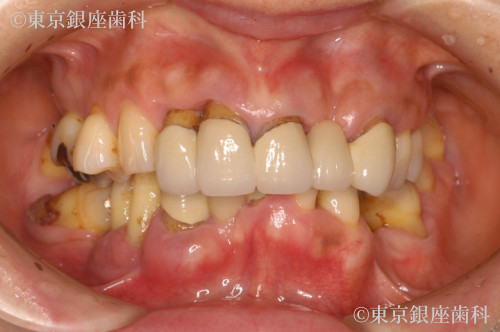

Before

疾患 歯周病

重度歯周病で上下インプラント治療を実施。術後に皮膚の湿疹・赤みが出たが、チタンアレルギーではなく経過観察で改善。現在も問題なく使用できている。

上下ワンデイインプラント

腫れ・痛み・出血、金属アレルギー疑い、補綴物劣化の可能性

皮膚症状(まれ)・術後疼痛